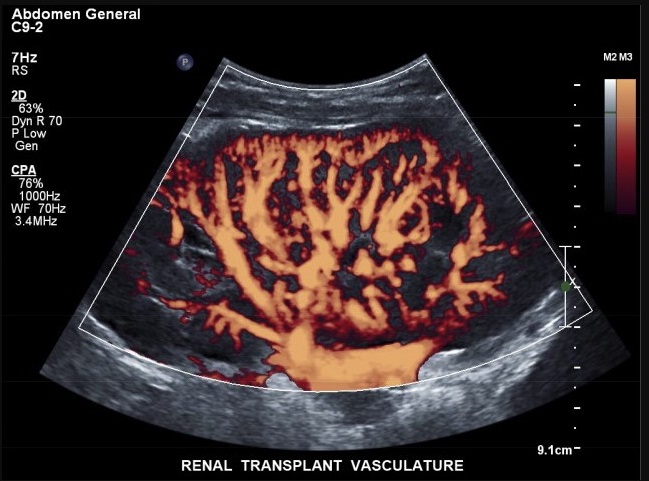

Power Doppler

این نوع داپلر به جای نمایش جهت و سرعت جریان خون، شدت یا توان سیگنال داپلر را نمایش میدهد. به دلیل حساسیت بالاتر به جریانهای آهسته، Power Doppler برای بررسی جریان خون در بافتهای کوچک یا عروق ضعیف مانند کلیهها و تومورها استفاده میشود.

از نظر فیزیکی، در این حالت توان کلی امواج بازتابی از ذرات متحرک اندازهگیری شده و در قالب رنگهایی با شدت متفاوت بدون در نظر گرفتن جهت جریان، نمایش داده میشود.